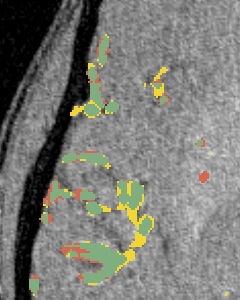

Vessel segmentation is an essential task in many clinical applications. Although supervised methods have achieved state-of-art performance, acquiring expert annotation is laborious and mostly limited for two-dimensional datasets with a small sample size. On the contrary, unsupervised methods rely on handcrafted features to detect tube-like structures such as vessels. However, those methods require complex pipelines involving several hyper-parameters and design choices rendering the procedure sensitive, dataset-specific, and not generalizable. We propose a self-supervised method with a limited number of hyper-parameters that is generalizable across modalities. Our method uses tube-like structure properties, such as connectivity, profile consistency, and bifurcation, to introduce inductive bias into a learning algorithm. To model those properties, we generate a vector field that we refer to as a flow. Our experiments on various public datasets in 2D and 3D show that our method performs better than unsupervised methods while learning useful transferable features from unlabeled data. Unlike generic self-supervised methods, the learned features learn vessel-relevant features that are transferable for supervised approaches, which is essential when the number of annotated data is limited.